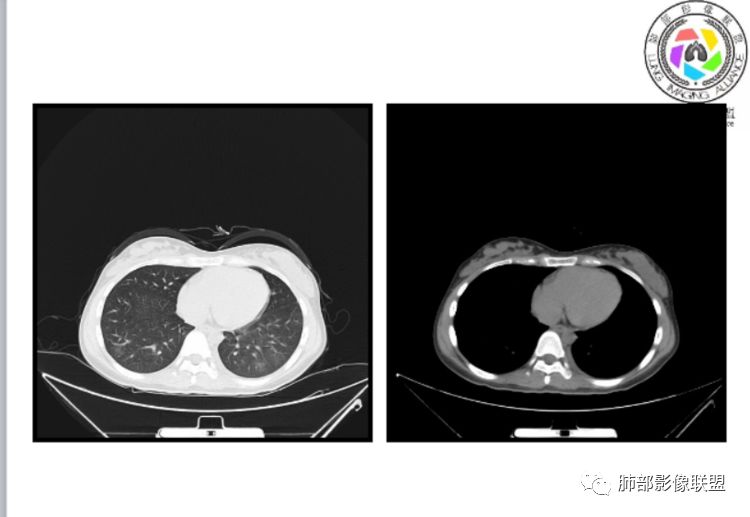

小微:右肺下叶斑片状密度增高影,抗炎治疗6天后复查,双肺下叶出现斑片状密度增高影,排除炎性病变,D2聚体特别高,考虑肺栓塞,肺梗死,建议增强扫描。王开金江津中心医院呼吸科:@岳微-辽宁PLA234医院放射科?支持,患者年轻女性,胸痛主诉,使用雌激素,高危人群,心率快,d二聚体升高,右下叶斑片加肺动脉明显增宽,抗感染无效,要考虑PTE,建议肺动脉ctpa。傅昌瑜:19岁,女性,右侧胸痛2天,发热以中度热为主,D—二聚体升高,肺动脉主干增宽,病灶位于胸膜下,抗感染后增多,近来有服用炔雌醇环丙孕酮片2周期史,诊断:肺栓塞,下一步完善肺CTPA检查。阿仙奴:青年女性,急性起病,胸痛入院,月经不调史,目前服用孕酮片。流感抗体阳性,d二聚体升高,无低氧血症。右肺下叶基底段胸膜下磨玻璃样改变,肺动脉增宽,治疗过程出现发热,复查左下叶胸膜下新发病灶。考虑:肺栓塞(服用孕酮相关)?奔跑的37°Doctor(陆喜红 ) :年轻女性,胸痛 急性病程,有服用雌激素避孕药史(是否有血液循环的改变,高凝状态),实验室D二聚体很高(也是提示血液高凝状态) ,第一次CT,右下肺胸膜下斑片状密度增高模糊影,肺动脉形态密度未见明显异常,抗炎后复查,肺动脉干及其分支,感觉增粗了一点,局部形态有点饱满,双下肺胸膜下片状影增多,锁定肺动脉栓塞应该不会错,建议CTA检查飞鹰行动:青年人,女性,右肺下叶斑片状密度增高影,抗炎治疗6天后复查无好转,,双肺下叶出现斑片磨玻璃影,主肺动脉增粗,结合患者服用的药物和D2聚体特别高,考虑肺栓塞,建议CTA。李:口服避孕药,有危险因素,肺动脉较主动脉增宽,D二聚体增高,胸膜下片状影,考虑肺栓塞;@晨义工张帅,医附属潞河医院呼吸?是否痰中带血很关键,不知有没有张帅:患者入院后第七天出现痰中带血风之子:病程中有发热,D—二聚体升高,肺动脉主干增宽,病灶分布于胸膜下,抗感染后增多,结合服药史诊断:肺栓塞,建议CTPA检查。不支持的地方是没有低氧血症,不明白为什么第二次复查ct双侧乳腺不对称,按理乳腺炎多见于哺乳期张帅:大家方向都在考虑肺栓塞:我提问两个问题:1 周围毛玻璃怎么回事?2左下肺小叶间隔增宽怎么回事?笨丫头:周围的磨玻璃应该考虑是肺梗死后出血渗出,同时合并机化性炎症小叶间隔增宽,我考虑应该是梗死后炎性渗出wonderful:我不支持肺栓塞 不能解释发热原因

笨丫头:肺栓塞也会发热呀王江涛:肺内子宫内膜异位症,合并梗死出血Lenle董:外围渗出性改变,出血?左下肺的支气管镜不会看张帅:呼吸困难比较难判断,尤其对于一个有胸痛的患者来说@唐大川新沂市人民医院呼吸科风之子:对,要警惕子宫内膜异位症岁月:病史:女,19岁;右侧胸痛2天;血常规17.4,中性粒75.7%,右下肺斑片影;月经不调,雌激素?治疗;D2高,3974.78,支气管镜阴性。治疗方式,抗炎。病史诊断方向:肺栓塞?影像:首先找肺栓塞影像。6天后CT可疑肺栓塞;作者量肺动脉23.7mm,提示什么?好像和同层面主动脉宽度相当,先心病?肺血无明显改变?双肺斑片影,左侧磨玻璃,边界清楚,还有些散在不清楚,左侧为甚,胸膜下贴,三角形?左侧少了胸水;诊断:肺栓塞;鉴别:先心合并肺栓塞?肺炎。

张帅:好多老师都在说肺动脉增宽。肺动脉增宽标准是多少?程磊:29。或者比同层主动脉比值大于等于1

张帅:我量的虽然不标准,但不到24

水晶石头:患者青少年女性,右侧胸痛2天就诊。有咳嗽,无痰。初次胸部CT:右下肺片状模糊影。入院后经头孢美唑、莫西沙星抗感染治疗6天后复查胸部CT:右下肺病灶加重,且左下肺出现类似病灶。结合其气管镜气道无异常,病程中有发热,D—二聚体升高,近来因月经不调有服用炔雌醇环丙孕酮片史。诊断考虑良性非感染性。肺栓塞可能性大,鉴别血管炎及子宫内膜肺异位可能。流心明智:女性,19岁,右侧胸痛2天,中度热为主,D—二聚体升高,影像:肺动脉主干小于29mm,病灶位于右下肺胸膜下,斑片影,胸膜侧宽基底,抗感染后增多,左下肺亦出現类似病灶,似有反晕、融冰征。近来有服用炔雌醇环丙孕酮片2周病史,考虑诊断:肺栓塞。具体性质及发病机制有待进一步检查。尘缘:@吴永丽 灌云县医院 呼吸?应该是的,左下肺的磨玻璃影像后面也支持有出血改变所以可能就是一个子宫内膜异位出血合并感染

CT平扫及间接征象:

1、一个或多个胸膜下斑片高密度影(梗死、出血、肺不张、肺水肿、炎性渗出),典型为胸膜下楔形影 ,尖端指向肺门

2、肺动脉高压(中心肺动脉扩张),有时可见肺动脉区高密度影。

3、肺血减少

4、马赛克灌注

5、膈肌升高、胸腔积液、心包积液

3.影像:病变胸膜下多发斑片影,提示与血管有关,早期病变为渗出,应该是早期的炎性渗出,病灶抗感染治疗后实变区增多、变大,临床症状又出现咯血,CT上应该合并了肺泡出血、梗死、肺不张及肺水肿;